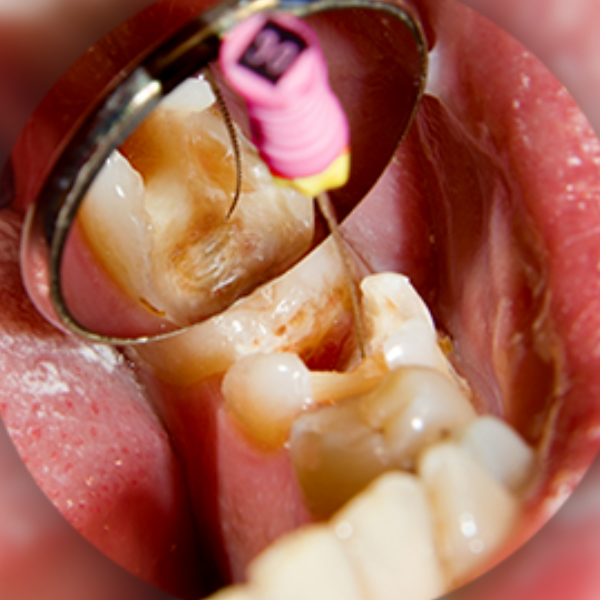

A root canal is a dental procedure that removes infected or damaged pulp from inside your toot, cleans and disinfects the area, and seals it with a protective filling or crown.

Root Canal Treatment

How it works